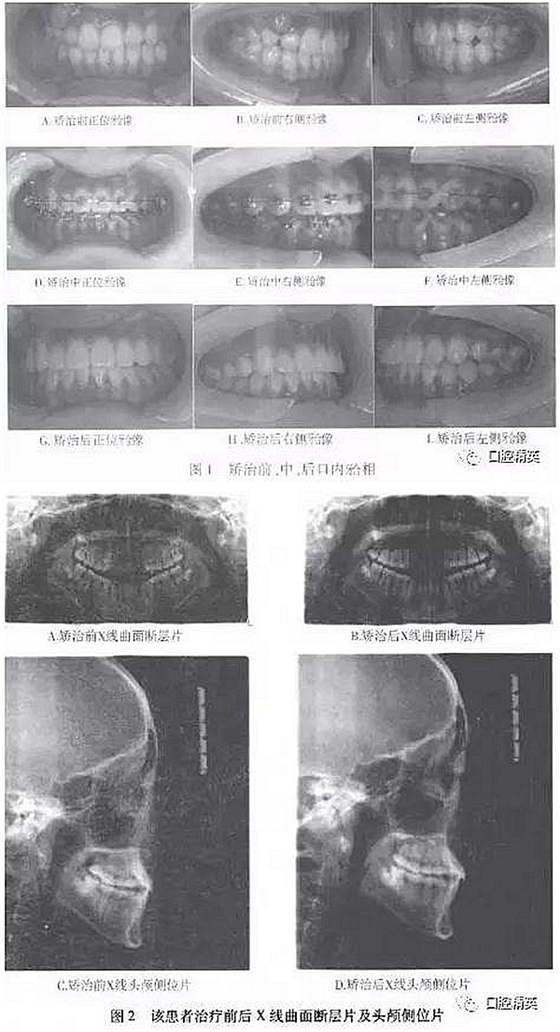

矯治結(jié)束后,患者上下牙合牙列整齊,前牙覆牙合、覆蓋正常,上下中線居中一致,雙側(cè)磨牙、尖牙均達(dá)中性關(guān)系。X線全景片顯示牙根發(fā)育及傾斜度正常,頭顱側(cè)位片顯示上頜齒槽骨得到進(jìn)一步發(fā)育,上頜骨突度達(dá)到正常值(見表1,圖1,2)。軟組織正面外貌改善顯著,面部左右對稱無偏斜。

④X線檢查:全口曲面斷層片顯示,上下牙臺四個象限均有智齒低位埋伏阻生;頭顱定位側(cè)位片測量分析結(jié)果見表1。